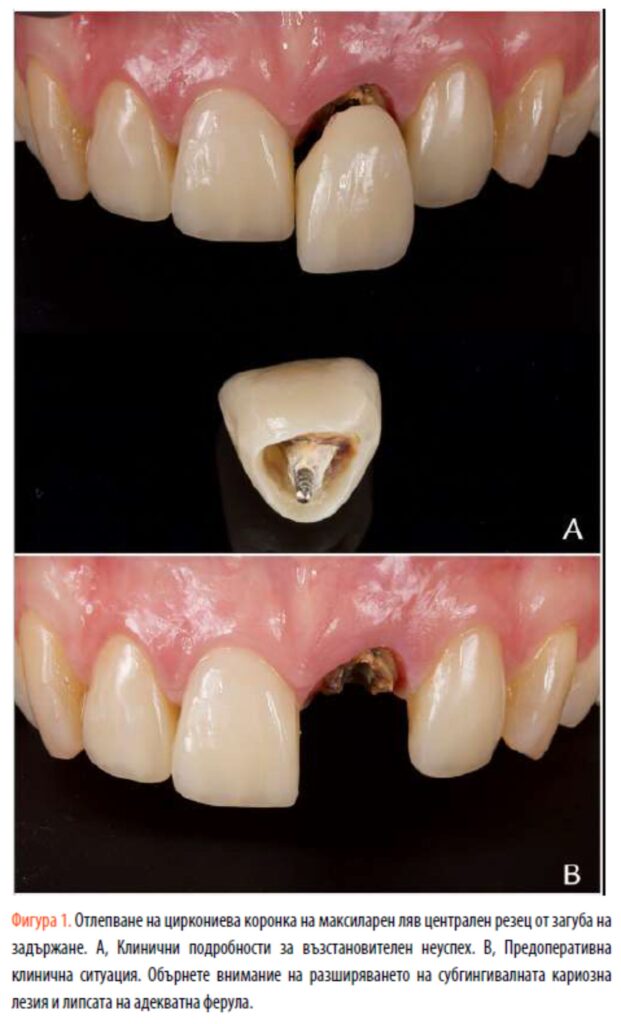

Жена на 55 години е насочена към частна практика за лечение на максиларен ляв централен резец. Тя съобщава за множество разлепвания на циркониева коронка върху зъба (фиг. 1A). Нейната медицинска история не е свързана със съпътстващи заболявания и тя не е била пушач. Останалият зъб имаше субгингивална кариозна лезия и недостатъчна ферула (фиг. 1B). Патологична подвижност не се наблюдава, а дълбочината на сондиране варира между 1,5 и 2 mm. Зъбът беше асимптоматичен при перкусия и палпация, а гингивалния ръб на зъба беше на същото ниво като максиларния десен централен резец. Ендодонтско повторно лечение не беше необходимо въпреки възможното коронарно изтичане, тъй като рентгенографското изследване показа добре обтуриран коренов канал и липса на периапикална лезия (фиг. 2А).